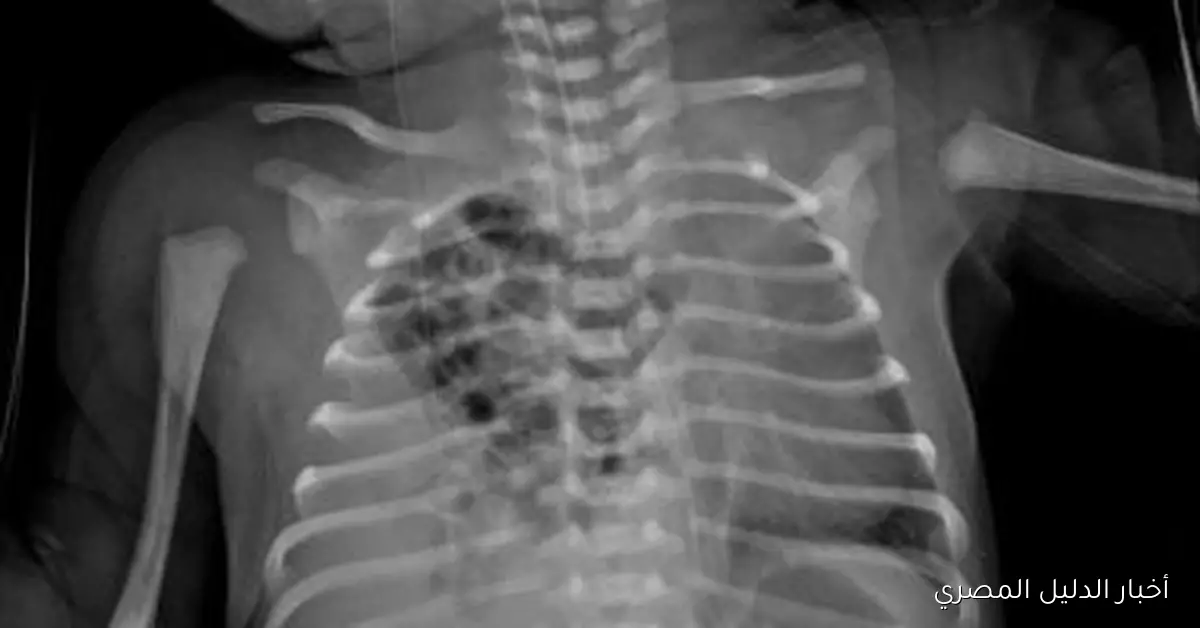

في إنجاز طبي بارز يضاف إلى سجل النجاح لقطاع الصحة في المنوفية، تمكن الفريق الجراحي بمستشفى زاوية الناعورة المركزي، بقيادة الدكتور مجدي لولح وبإشراف الدكتور إسلام الفقي مدير المستشفى، من إجراء عملية نادرة لإصلاح فتق بالحجاب الحاجز من نوع بوكدالك في الجهة اليمنى، وتعتبر هذه الحالة من الحالات النادرة التي لا تتجاوز نسبتها عالميًا 10-15% من إجمالي حالات الفتق الحجاب الحاجز الخلقي، ويأتي هذا الإنجاز تنفيذًا لتوجيهات الدكتور خالد عبد الغفار نائب رئيس مجلس الوزراء ووزير الصحة والسكان واللواء إبراهيم أبو ليمون محافظ المنوفية، وذلك لتقديم خدمات صحية ذات جودة عالية تلبي احتياجات المواطنين، بالإضافة إلى تعليمات الدكتور عمرو مصطفى محمود وكيل وزارة الصحة بالمنوفية بالارتقاء بمستوى الخدمات الطبية المقدمة في جميع أنحاء المحافظة.

خلال العملية، اكتشف الفريق الطبي وجود الفص الأيمن من الكبد داخل التجويف الصدري، إلى جانب الأمعاء الدقيقة والغليظة، مما أدى إلى ضغط على الرئة اليمنى، وقد قام الأطباء بإرجاع جميع الأعضاء إلى وضعها الطبيعي داخل تجويف البطن، ثم تم إصلاح الفتق باستخدام خيوط غير قابلة للذوبان من نوع “إيثيبوند” لضمان المتانة واستقرار الحالة.